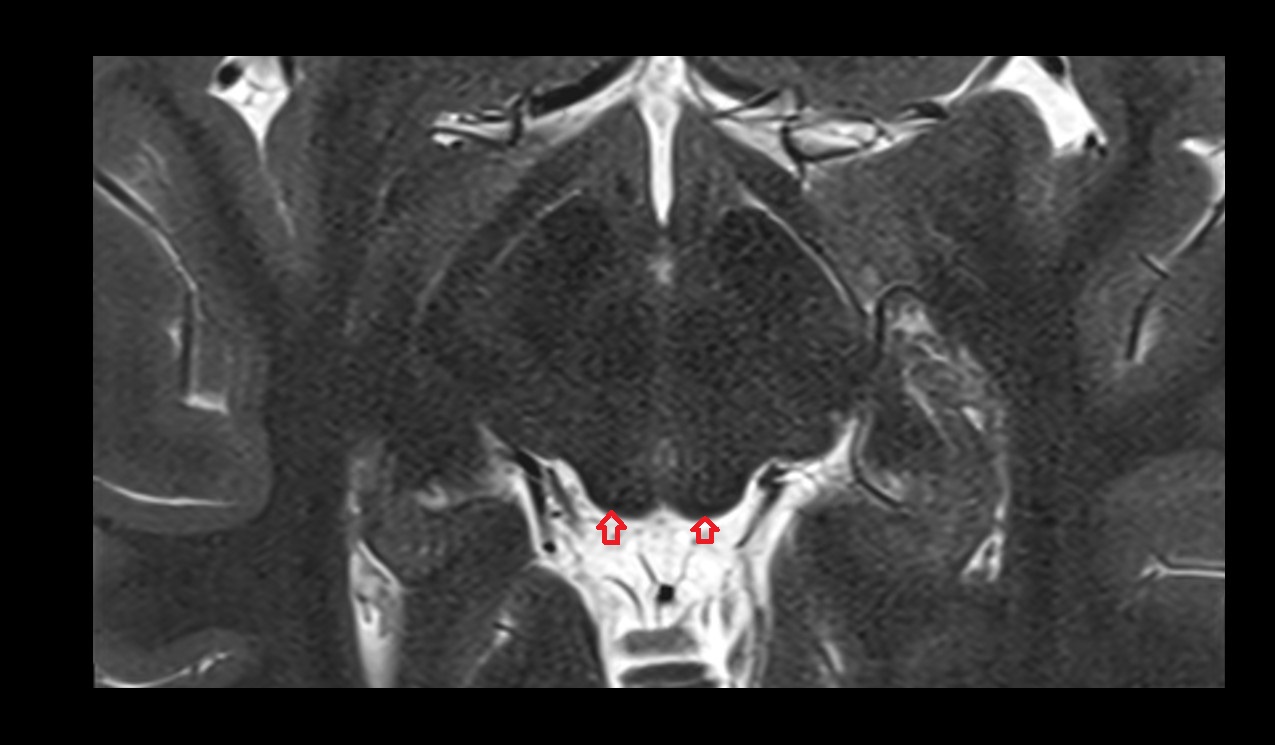

- Peripheral zone of prostate

- Anterior Fibromuscular Stroma of prostate

- Central zone of prostate

- Transitional zone of prostate